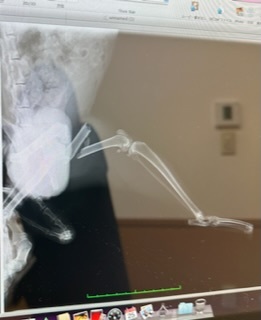

10日前から左足を引きずって歩いてました。

レントゲンの結果『左大腿骨骨折』

大腿骨がバキッと折れてました😱

入院して、明日手術していただきます💉